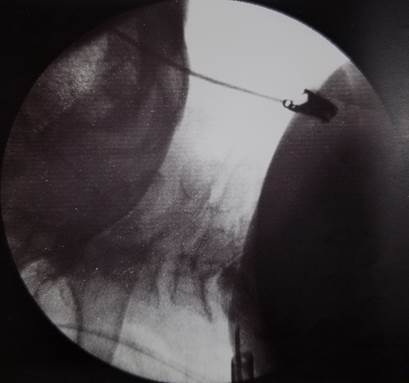

Se procede a realizar biopsia ósea de la vértebra cervical y el diagnóstico anátomo-patológico fue osteomielitis crónica sin signos de malignidad (Figura 3).

Se descarta la hipótesis diagnóstica de neoplasia de columna cervical y se confirma la hipótesis de osteomielitis.